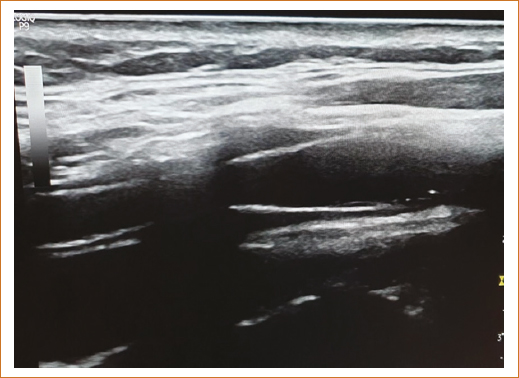

El 25 de enero de 2020 se procedió a practicar panangiografía de troncos supraaórticos y carótidas, bajo el siguiente protocolo intervencionista: cateterismo de vasos del cuello con panangiografía por vía femoral derecha, usando proyecciones ortogonales en anteroposterior, lateral, oblicuas y posiciones especiales usando un catéter guía MATCH 1 de calibre 7 Fr con ayuda de una guía Terumo de 0.032”. En la arteria carótida común derecha no se observaron placas ateromatosas, y tampoco en su ramas interna y externa, la arteria carótida interna común izquierda sin lesiones, la arteria carótida externa izquierda sin lesiones, la arteria carótida interna izquierda con lesión estenótica grave del 90% en su origen y placa focal extensa sin afectación de la bifurcación (Fig. 1). Las arterias subclavias no presentaban zonas de estenosis significativas. Se llevó a cabo un cateterismo cardiaco protocolario por vía radial derecha realizando stenting carotídeo izquierdo con ascenso de un catéter guía multipropósito Match 1 de calibre 7 Fr con una guía hidrófila Terumo de 0.032” posicionándose en la arteria carótida común izquierda 3 cm por debajo de la bifurcación. Se practicó ascenso wallstent 7 × 40 mm con una guía ChoICE PT extrasoporte de 0.014” y se liberó un stent de distal (arteria carótida interna izquierda) a proximal (arteria carótida común izquierda), observando una estenosis residual del 50%, por lo que se avanzó un balón HIRYU de 5 × 10 mm con el que se posdilató a 16 atm, con un resultado final exitoso de solo un 20% de estenosis residual (mejoría del 70%) (Fig. 2). Termina el procedimiento asintomática cardiovascular e íntegra neurológicamente, se retira el introductor femoral y se coloca un dispositivo de cierre vascular Angio-Seal de 6 Fr. Hallazgos: 1) tronco coronario izquierdo ligeramente sinuoso, sin lesiones significativas; 2) arteria circunfleja ligeramente tortuosa, sin zonas de estenosis; 3) arteria descendente anterior un poco más sinuosa, sin zonas de estenosis; y 4) arteria coronaria derecha de trayecto muy regular, de muy buen calibre, sin imágenes de estenosis. Se concluyó el cateterismo cardiaco sin incidentes clínicos ni complicaciones, con el sumo cuidado de optimizar la dosis del medio de contraste (solo se usaron 25 ml).

Figura 2. Arteria carótida interna izquierda tras la intervención.

La paciente continuó con manejo médico con restricción hídrica, insulina de acción rápida por requerimientos, furosemida 10 mg/12 h, apixabán 2.5 mg/12 h, atorvastatina 40 mg/24 h y esomeprazol 40 mg/24 h por vía intravenosa. No presentó deterioro de la función renal y en las siguientes 72 horas la nueva depuración de creatinina se reportó en 42 ml/min. Metabólica y hemodinámicamente continuó compensada y neurológicamente consciente, orientada, Glasgow 15 puntos, sin déficit motor focal, movilizando sus cuatro extremidades con fuerza muscular normal, reflejos de estiramiento muscular normales acorde a su edad, no disártrica, no disfágica, sin ataxia, íntegra de juicio y raciocinio, marcha normal, tolerando la vía oral y sin compromiso en sitios de arteriopunción. La paciente egresó por mejoría 5 días después del cateterismo, con tratamiento multidisciplinario y seguimiento en la consulta externa de medicina interna. Desde entonces hasta septiembre de 2025 presenta mejoría de su clase funcional cardiaca, estabilidad metabólica con HbA1c < 7.4% y estabilidad hemodinámica con presión arterial promedio 146/84 mmHg. El ultrasonido Doppler carotídeo de control tardío del 11 de septiembre 2025 mostró stent carotídeo estable, con adecuado flujo sanguíneo (Figs. 3 y 4). Las radiografías simples de cuello permitieron identificar fácilmente el stent, su ubicación y la ligera estenosis residual (Fig. 5).